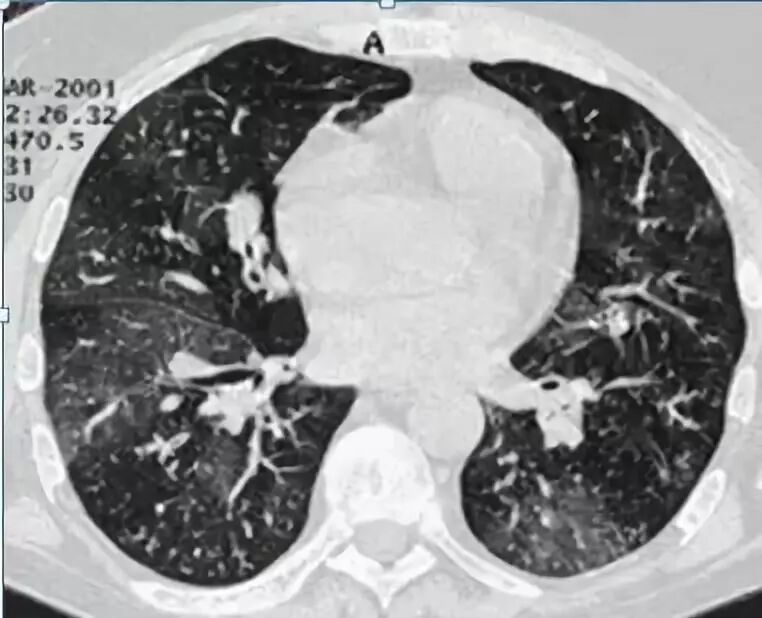

一般而言,弥漫性生长的多数是良性病变,局灶性生长的可能为恶性。

弥漫性的 GGO

总结一下,GGO 如果是弥漫性的,一般不是恶性的,如果是局灶性的要当心一点,特别小的仅需随访。注意让患者增强体质,如果病灶变大变实多数是早期肺癌,目前微创手术能够根治。